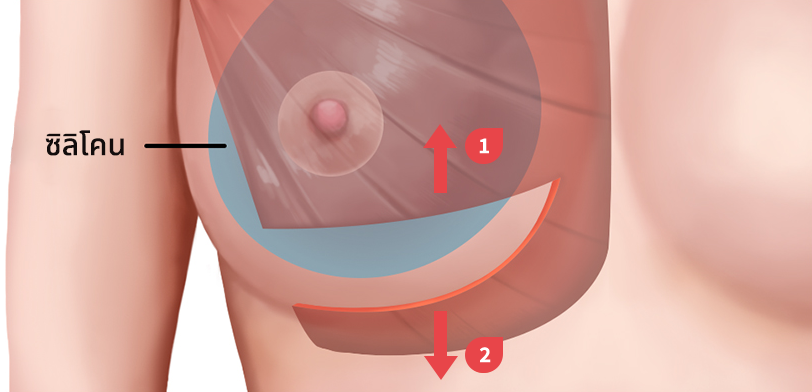

ผ่าตัดส่วนล่างของกล้ามเนื้อหน้าอกส่วนบน

เมื่อกรีดกล้ามเนื้อออก เนื่องจากแรงดึงของกล้ามเนื้อ ทำให้ส่วนบนของกล้ามเนื้อหดตัวและด้านล่างของกล้ามเนื้อจะยึดติดกับด้านล่าง

ใส่ซิลิโคนระหว่างกล้ามเนื้อที่ถูกกรีด ส่วนบนของซิลิโคนอยู่ด้านล่างของกล้ามเนื้อหน้าอก ส่วนล่างของซิลิโคนอยู่ด้านบนของกล้ามเนื้อหน้าอก

ดึงส่วนบนของกล้ามเนื้อขึ้น

กล้ามเนื้อส่วนล่างจะยึดติดกัน

เทคนิคแบบ Dual Plane กล้ามเนื้อหดตัวลงและเคลื่อนที่ขึ้น

ผิวหนังและเนื้อเยื่อที่เชื่อมต่อกันค่อนข้างยืดได้ดี จึงสามารถสร้างเส้นโค้งตามธรรมชาติได้